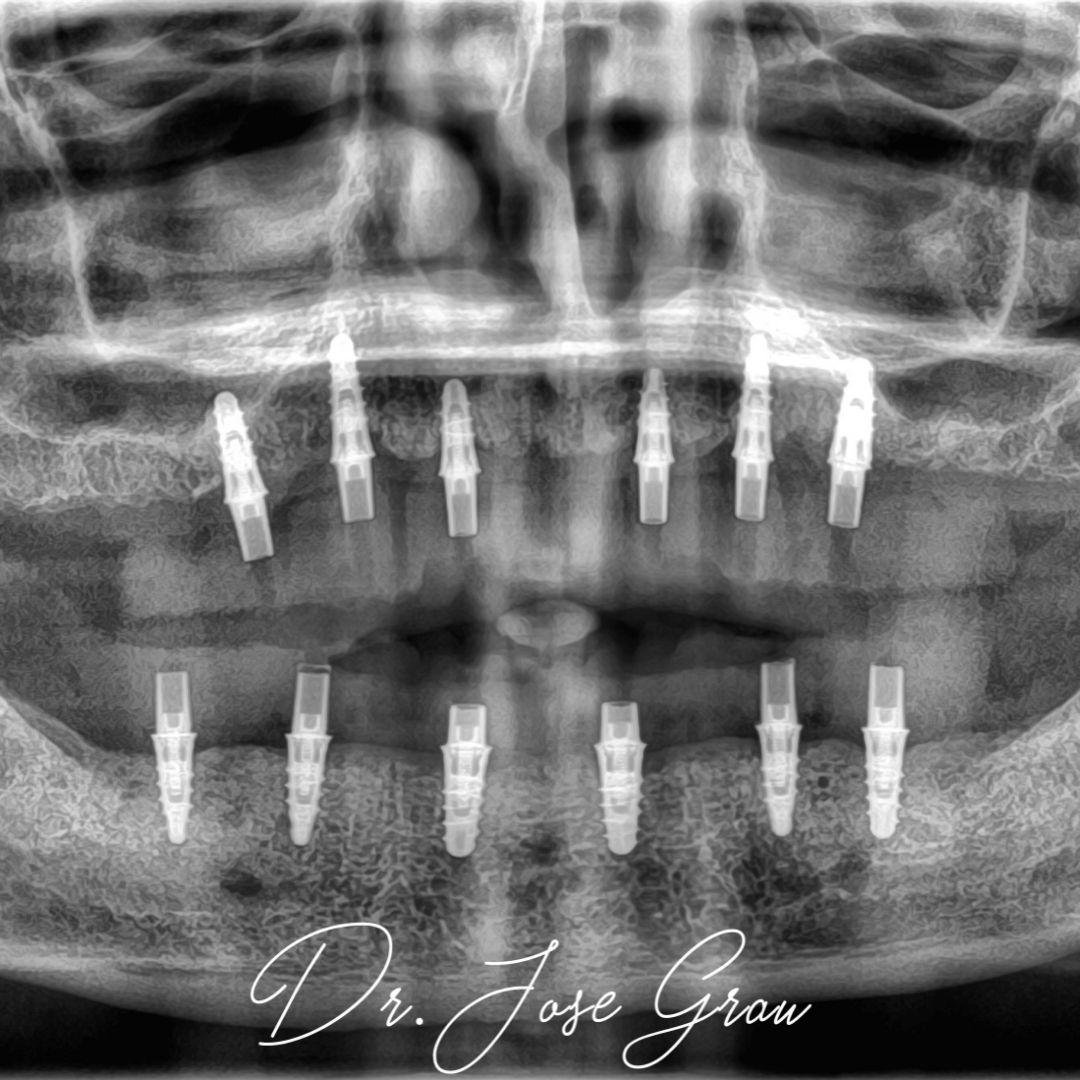

Rehabilitación bimaxilar flapless